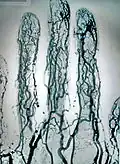

Angiographie cérébrale

Elle est l’application de la méthode de l’angiographie au niveau cérébral. Elle est utilisée en diagnostique et en interventionnelle. Les principales pathologies sont des dilatations des vaisseaux (anévrismes), le rétrécissement de vaisseaux (sténose) ou le blocage.

Elle est utilisée pour diagnostiquer des anomalies sur les vaisseaux sanguins du cerveau ou menant au cerveau (carotides). Ces différentes pathologies vasculaires peuvent être : un blocage (thrombose) ou un rétrécissement (sténose) d’un vaisseau, un anévrisme, une malformation artério-veineuse. On peut réaliser cet examen en préopératoire afin d’observer le système d’irrigation du cerveau. L’angiographie cérébrale permet également de diagnostiquer des pathologies non directement liées au système vasculaire mais ayant une influence sur celui-ci. Elle permet de visualiser des tumeurs, des œdèmes, des hernies, des vasospasmes, l’augmentation de la pression intracrânienne et l’hydrocéphalie.

L’apparition de nouvelles techniques d’imagerie non invasives a réduit l’importance de l’utilisation de l’angiographie cérébrale. On peut citer l’angioscanner, l’échographie doppler, l’angio-imagerie par résonance magnétique. Mais l’angiographie peut être recommandée après un examen précédent, afin d’apporter des informations complémentaires qui ne sont pas visibles par les nouvelles technologies. L’angiographie cérébrale reste l’examen le plus précis dans l’étude de la morphologie des vaisseaux sanguins, ainsi que pour fournir des données dynamiques sur la circulation.